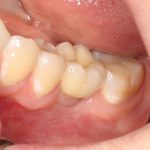

И вот, в жизни Марии наступил долгожданный день — окончательная фиксация керамических коронок на установленные имплантаты:

При этом, она ни дня не оставалась без зубов, была полностью социализирована и жила обычной жизнью. Спустя 5 месяцев после удаления, поставленную Марией клиническую задачу можно считать решёной. Но это с её точки зрения. С нашей же, всё самое интересное только начинается.

Вот клиническая картина и рентгенологический контроль через 2,5 года после имплантации и протезирования:

Как видите, под приемлемыми объёмами и состоянием десны в области имплантатов скрывается надёжный фундамент — восстановленная и сохраненная с помощью аугментации костная ткань, состояние которой за два с половиной года только улучшилось.

С точки зрения функционала, Мария не чувствует принципиальной разницы между естественными здоровыми зубами и коронками на имплантатах (последние она находит «более симпатичными») По её словам, она и думать забыла об имплантатах, а прошлые мучения с зубами кажутся ей «ночным кошмаром».